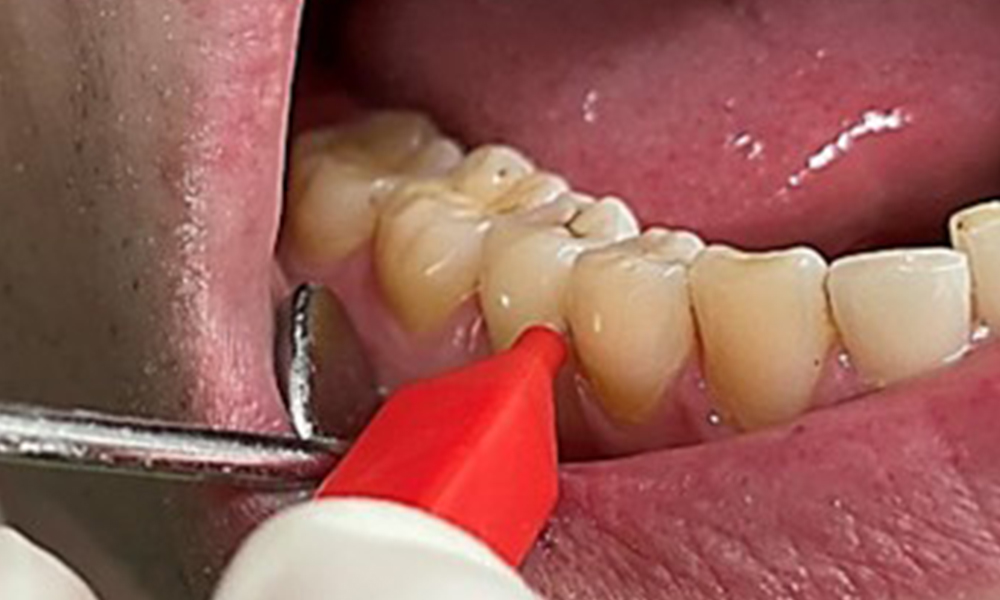

Instruction and motivation are important components of these appointments. Good home-based intraoral hygiene behaviour and understanding are important for patients. Plaque accumulation is particularly evident in the cervical regions (Fig. 8).

The arrows indicate plaque accumulations in the cervical region

Fig. 8: The arrows indicate plaque accumulations in the cervical region, © Dr R. Krapf

These must be discussed with the patient, and improvements to the teeth-brushing technique must be practised. A soft toothbrush attachment is recommended for home-based intraoral hygiene due to the presence of erosions and attritions.